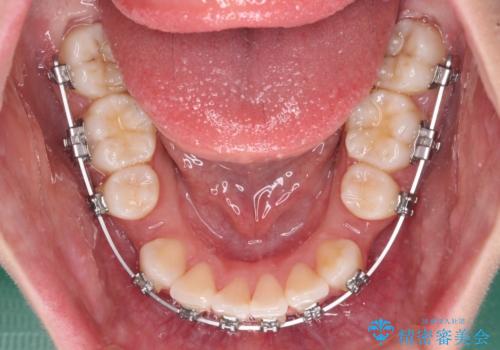

- メタルブラケット

- 歯のデコボコや八重歯、クロスバイトを気にして来院された患者様です。

上下左右第一小臼歯4本を抜歯し、ワイヤー装置にて歯列を整え、さらには少しでも口元を引っ込めるよう矯正治療を行うこととしました。